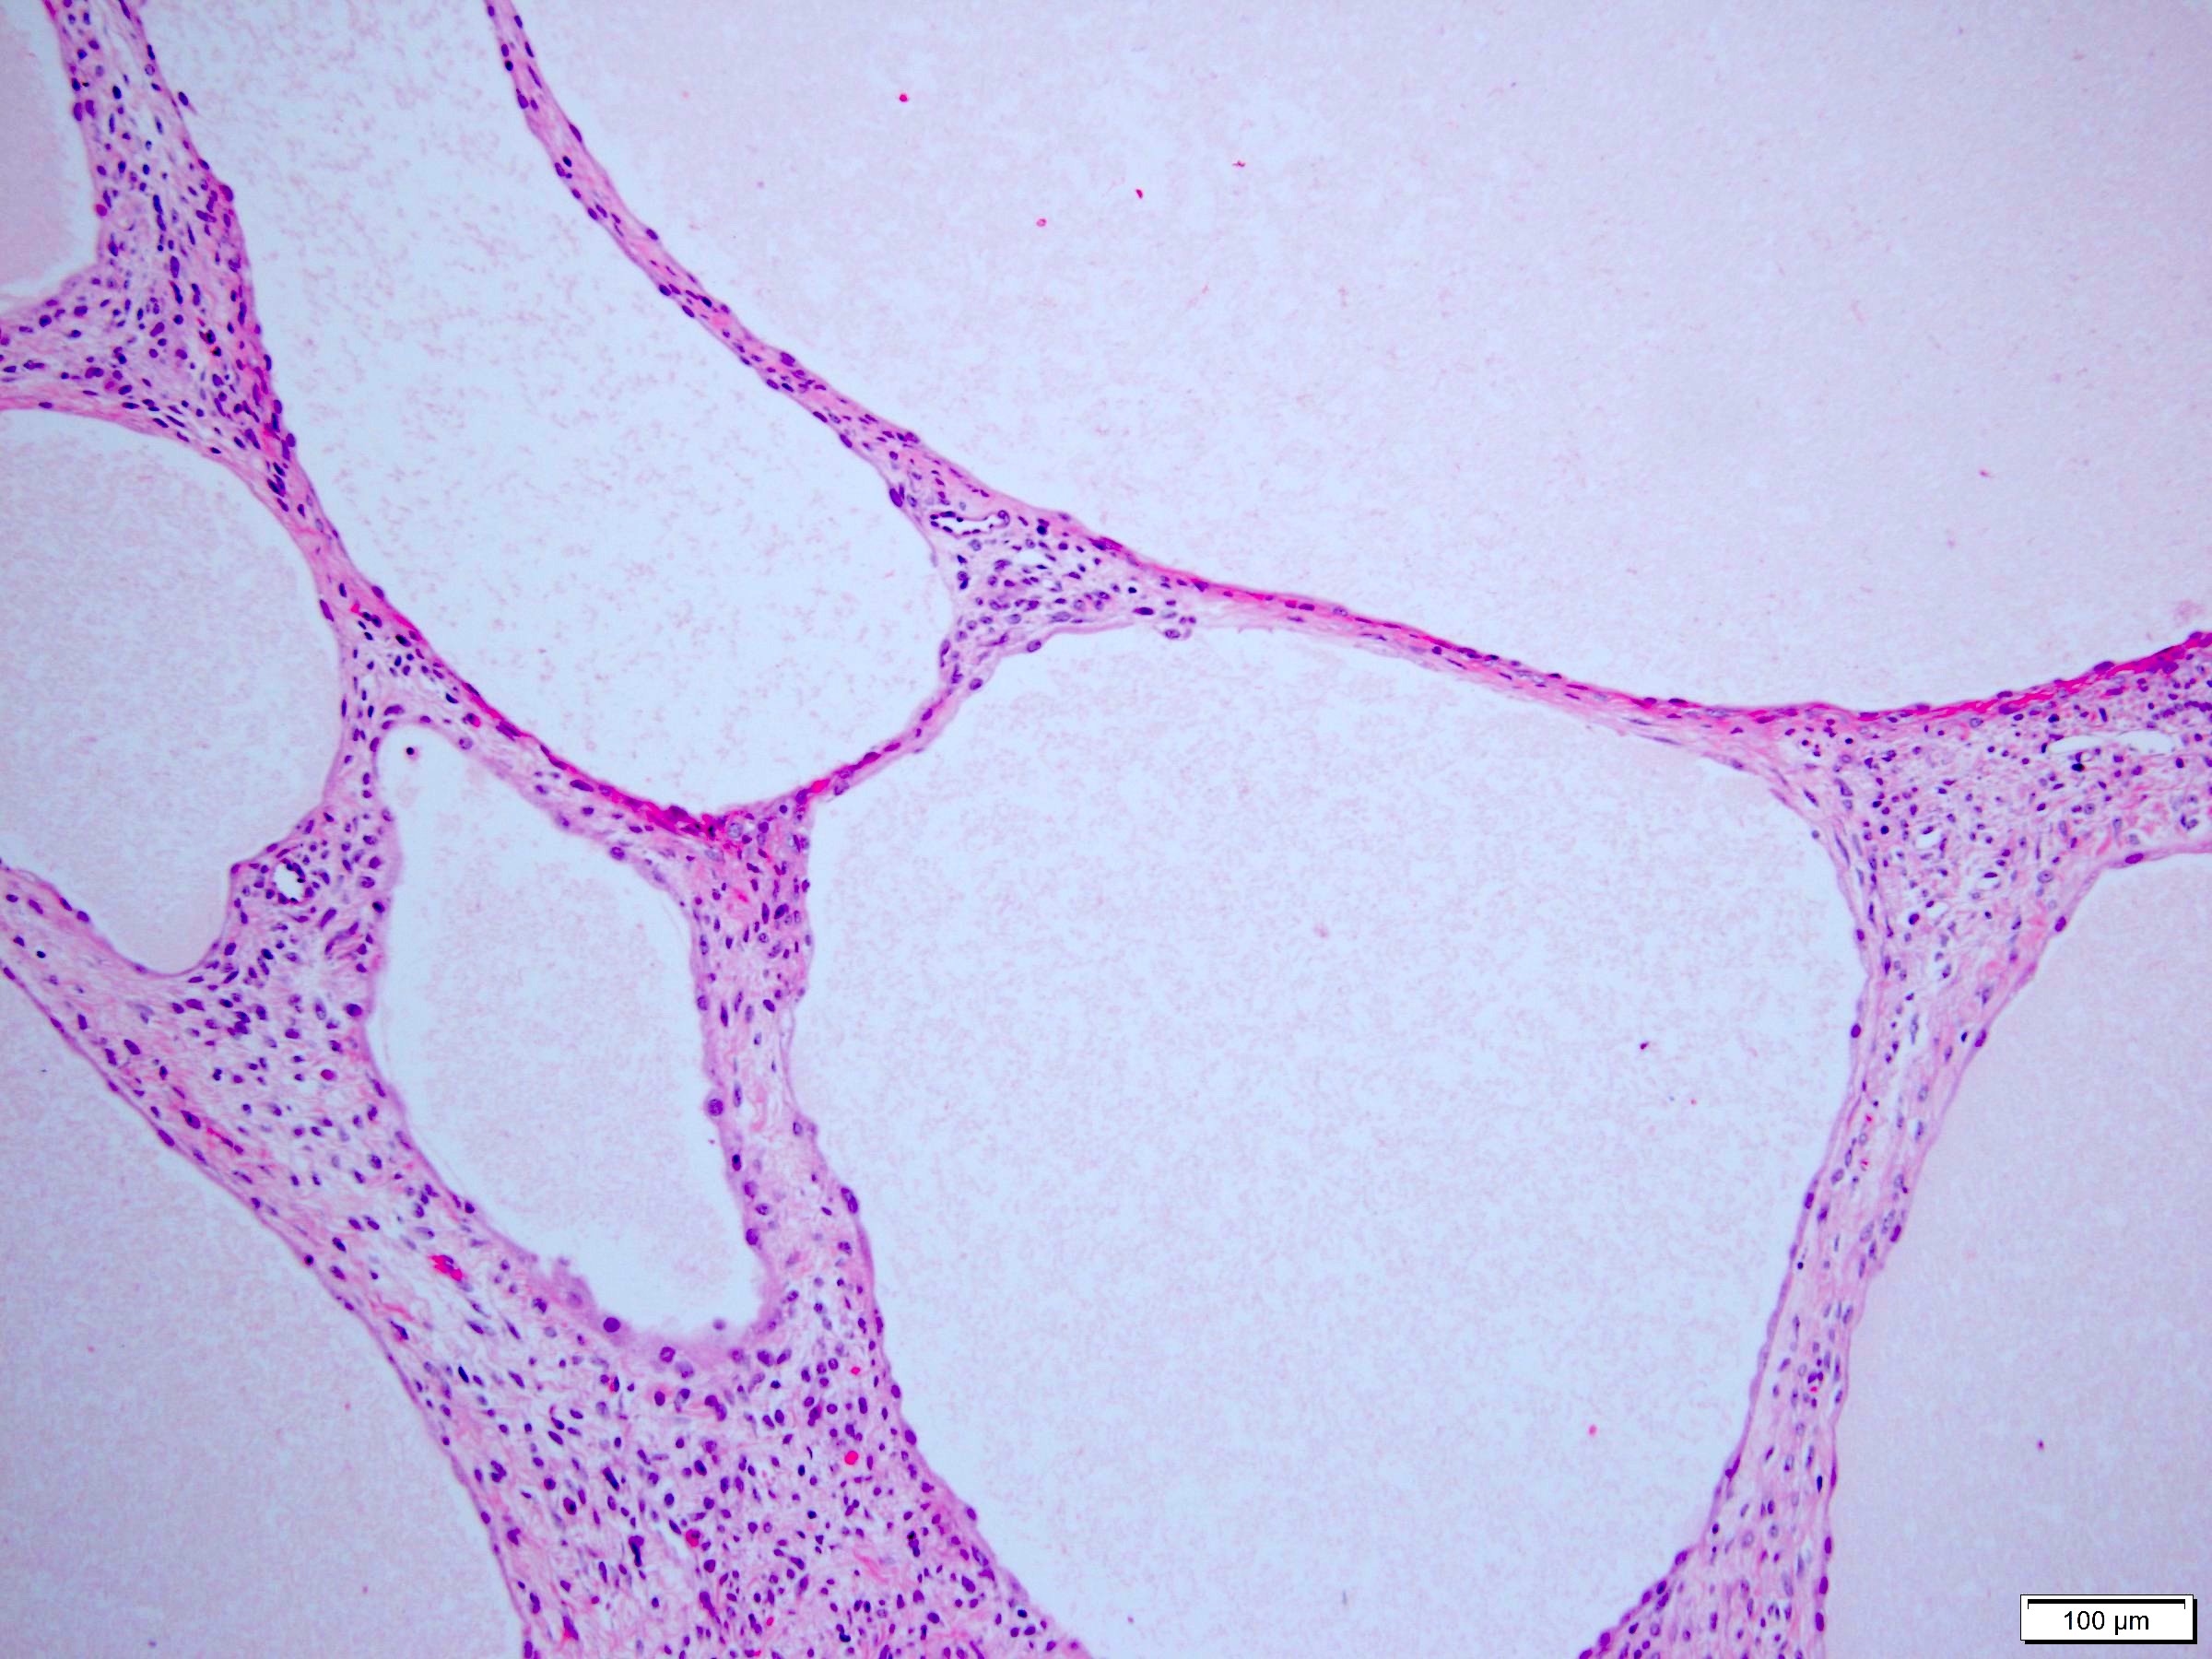

Microscopic (histologic) description

- Many with at least a partial pseudocapsule

- Entirely composed of cysts separated by septa (Semin Diagn Pathol 1998;15:2, Arch Pathol Lab Med 2004;128:1404, Am J Surg Pathol 2007;31:489, Eur Urol 2008;54:1237, Am J Surg Pathol 2016;40:1591)

- Stroma:

- Hypocellular to hypercellular

- Collagenous and fibrous to edematous and myxoid

- Areas of hyalinized stroma with contours resembling ovarian corpora albicantia

- Spindle cells; closely packed areas resemble ovarian stroma

- Cellular foci embedded with epithelial elements ranging from handful of cells with no lumen to tiny cysts with pinpoint lumens and to slightly larger cysts

- Steroidogenic cells: small clusters of polygonal cells with amphophilic cytoplasm and round nuclei, frequently around epithelial component

- Calcifications, multinucleated giant cells, foamy or hemosiderin laden macrophages and focal chronic inflammation

- Epithelium:

- Cells lining cysts

- Mostly arranged in single layer with various morphology: flat, cuboidal, hobnail, clear cell

- Rarely, foci of blunt and delicate papillae or foci of multiple layers of epithelium

- Minimal cytologic atypia

- Rare necrosis, no mitosis

Microscopic (histologic) images

A 6 cm predominantly well circumscribed, multicystic mass was incidentally found in a 55 year old woman. Sections of the partial nephrectomy showed the above histologic features. The stromal component is positive for ER and PR (shown above). What is the likely diagnosis?